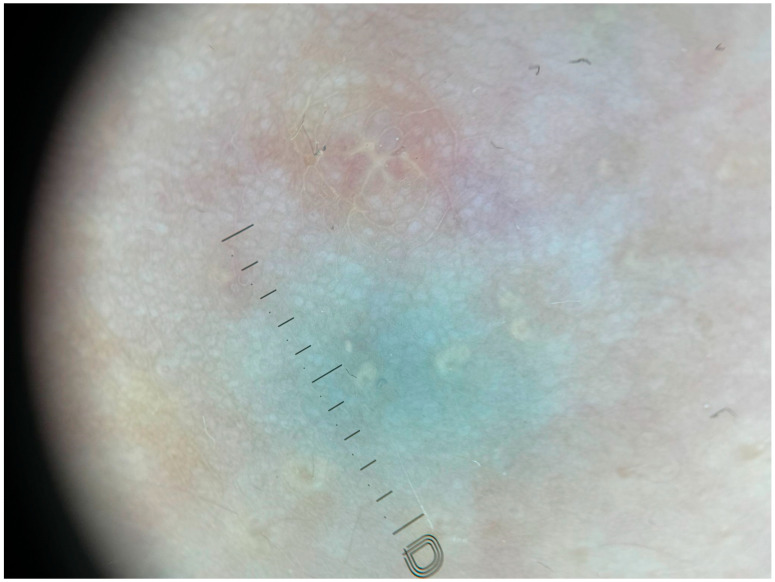

背景/目的:青春期女孩乳头的蓝绿色变色常常使诊断陷入困境。方法:我们描述了一个11岁的女孩谁发展双边和对称的蓝绿色斑疹在乳晕后区域超过八个月。皮肤镜及超音波检查显示为良性乳晕后囊肿,未见恶性肿瘤或其他徵状。鉴别诊断如血管畸形、血管瘤、血肿和蓝色痣被仔细考虑并根据临床和影像学结果排除。结果:诊断为双侧乳晕后囊肿。患者接受保守治疗,超声随访1年无变化。结论:本病例强调了全面评估的重要性,以避免不必要的侵入性手术,保护青春期乳房的微妙发育。

Background/Objectives: Bluish-green discoloration of the nipples in pubertal girls often poses a diagnostic dilemma. Methods: We describe the case of an 11-year-old girl who developed bilateral and symmetrical bluish-green macules in the retroareolar area over eight months. Dermoscopic and ultrasound examinations revealed benign retroareolar cysts, with no signs of malignancy or other alarming features. Differential diagnoses such as vascular malformations, hemangiomas, hematomas, and blue nevi were carefully considered and excluded based on clinical and imaging findings. Results: A diagnosis of bilateral retroareolar cysts was established. The patient underwent conservative management, and ultrasound follow-ups over one year showed no changes. Conclusions: This case underscores the importance of thorough evaluation to avoid unnecessary invasive procedures and to protect the delicate development of the pubertal breast.